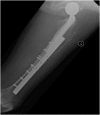

We report an 85-year-old patient with severe osteoporosis who had suffered from multiple episodes of periprosthetic fracture of the femur. Revision fixation with long-spanning cable plate for bisphosphonate-induced atypical periprosthetic femoral fracture was performed. Nonunion and implant failure occurred at 16 months requiring revision surgery using long-stem femoral prosthesis with cable-plate fixation. To further facilitate bone healing, allograft and bone morphogenetic protein (BMP) were added. Eventually bone union was achieved after one year.